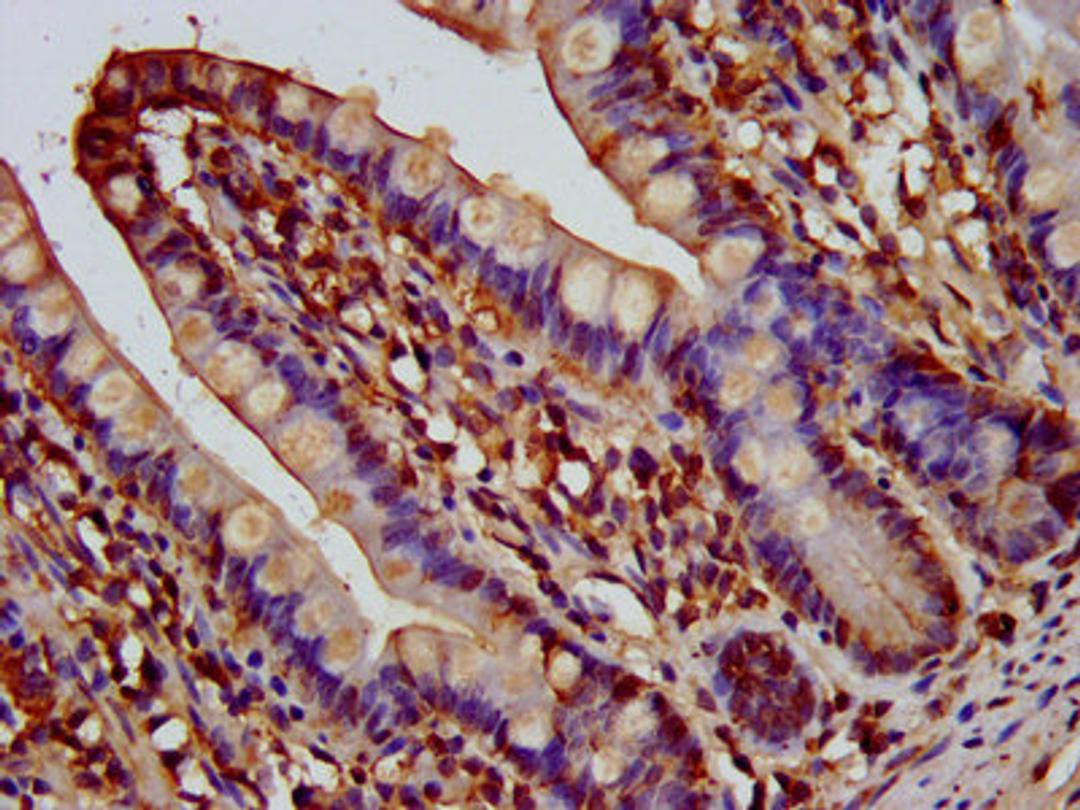

IHC image of CSB-PA853482LA01HU diluted at 1:200 and staining in paraffin-embedded human small intestine tissue performed on a Leica BondTM system. After dewaxing and hydration, antigen retrieval was mediated by high pressure in a citrate buffer (pH 6.0). Section was blocked with 10% normal goat serum 30min at RT. Then primary antibody (1% BSA) was incubated at 4°C overnight. The primary is detected by a biotinylated secondary antibody and visualized using an HRP conjugated SP system.